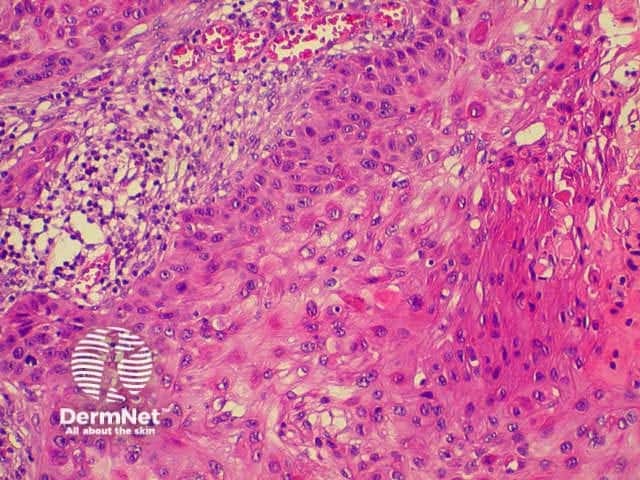

The histological characteristics of keratinocytic tumours are illustrated below.

Squamous cell carcinoma